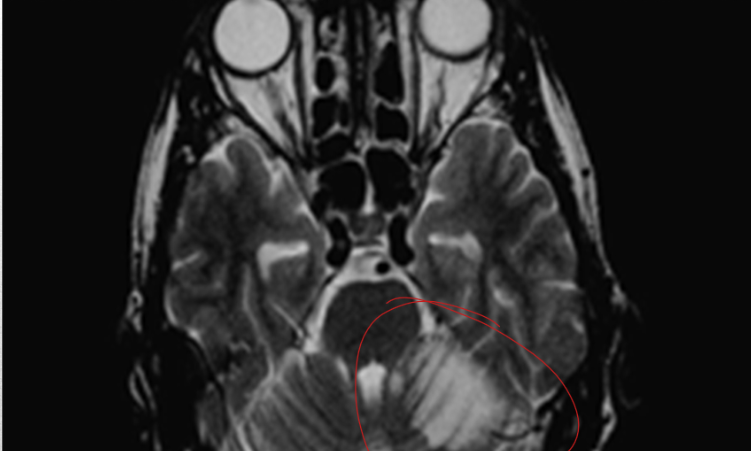

occlusion of these arteries leads to vertigo, n/v, nystagmus, ipsilateral limb ataxia, and contralateral spinothalamic sensory loss of the limb. if massive infarction occurs then this can lead to coma, tonsillar herniation and death

cerebellar artery infarct